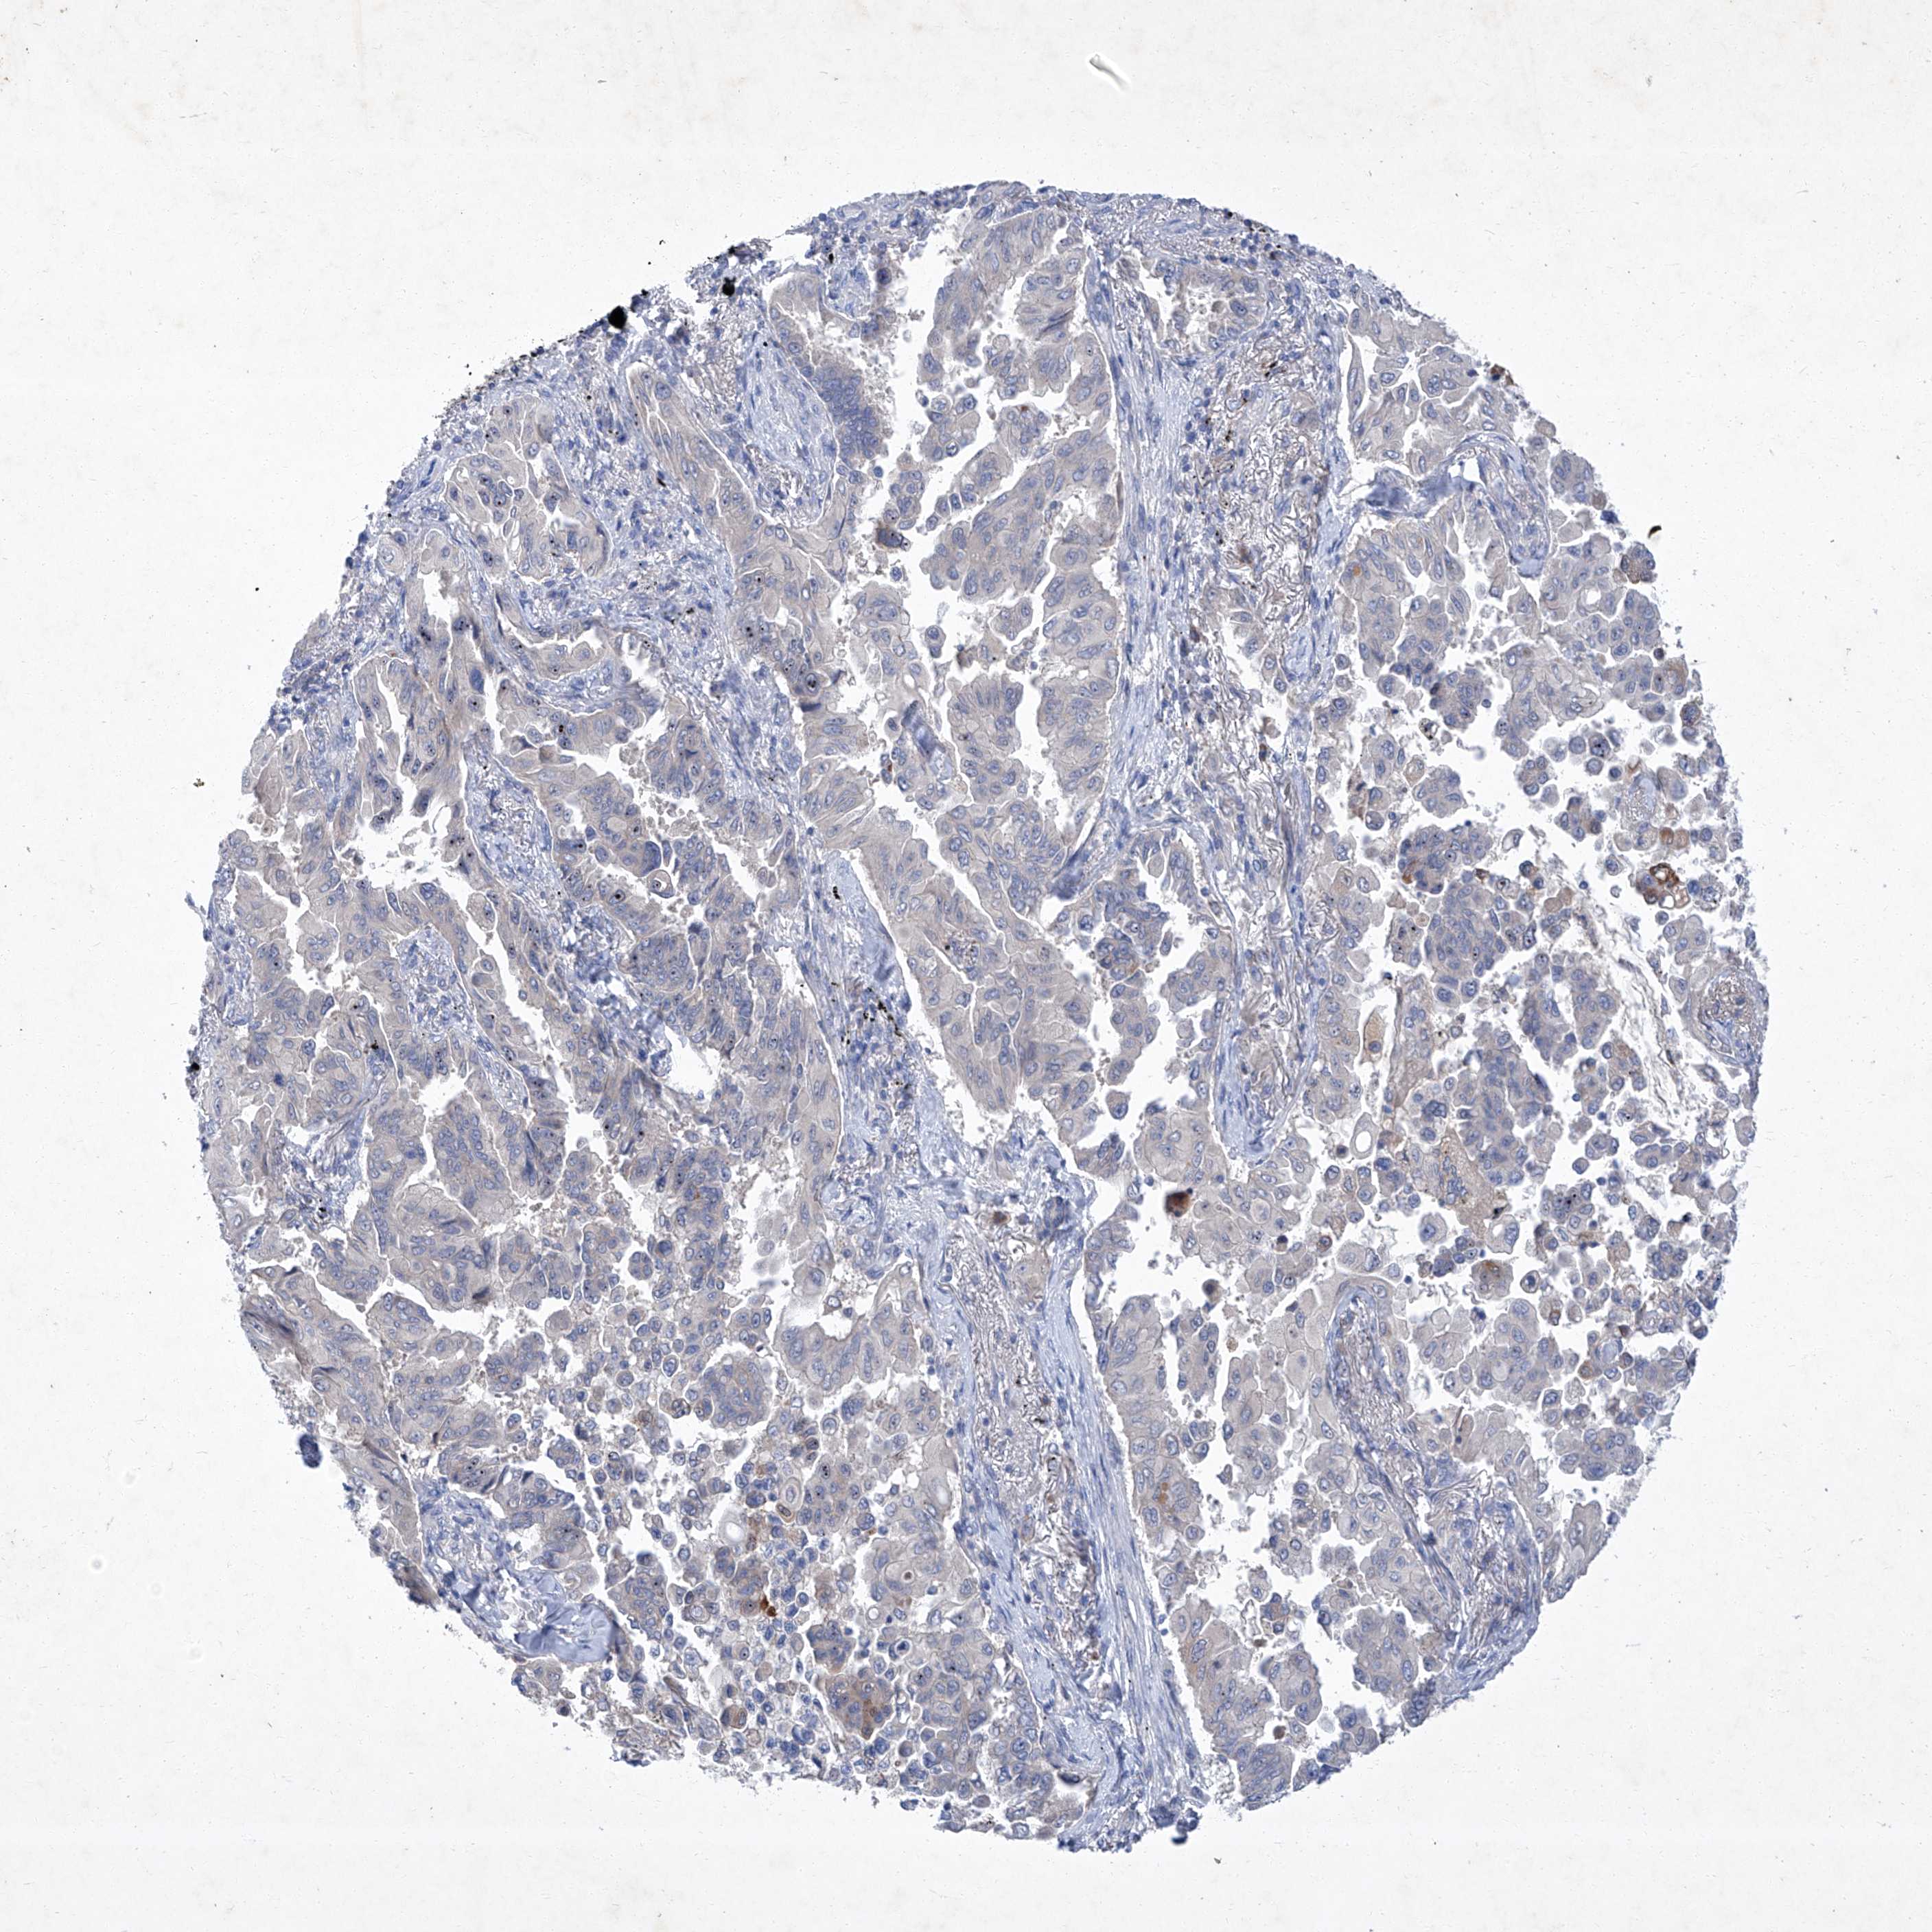

LUNG SQUAMOUS CELL CARCINOMA (TCGA) - Interactive survival scatter ploti

The Survival Scatter plot shows the clinical status (i.e. dead or alive) for all individuals in the patient cohort, based on the same data that underlies the corresponding Kaplan-Meier plots. Patients that are alive at last time for follow-up are shown in blue and patients who have died during the study are shown in red.

The x-axis shows the expression levels (FPKM) of the investigated gene in the tumor tissue at the time of diagnosis. The y-axis shows the follow-up time after diagnosis (years). Both axes are complimented with kernel density curves demonstrating the data density over the axes. The top density plot shows the expression levels (FPKM) distribution among dead (red) and alive patients (blue). The right density plot shows the data density of the survived years of dead patients with high and low expression levels respectively, stratified using the cutoff indicated by the vertical dashed line through the Survival Scatter plot. This cutoff is automatically defined based on the FPKM cutoff that minimizes the p-score. The cutoff can be changed by dragging the vertical line or by entering a cutoff value in the square labeled "Current cut-off".

Under the Survival Scatter plot the p-score landscape (black curve; left axis) is shown together with dead median separation (red curve; right axis). Dead median separation is the difference in median mRNA expression between patients who have died with high and low expression, respectively. It is calculated as follows: median FPKM expression of dead patients with high expression - median FPKM expression of dead patients with low expression. This is intended to aid the user in visually exploring custom cutoffs and the associated p-scores and dead median separation.

Individual patient data is displayed and can be filtered by clicking on one or more of the category buttons on the top of the page. Categories describing expression level and patient information include: high, low, alive, dead, female, male and tumor stages. The scale of the x-axis can be toggled between linear and log-scale by clicking on the "x log" button. Mouse-over function shows TCGA ID, patient information and mRNA expression (FPKM) for each patient.

& Survival analysisi

Kaplan-Meier plots summarize results from analysis of correlation between mRNA expression level and patient survival. Patients were divided based on level of expression into one of the two groups "low" (under cut off) or "high" (over cut off). X-axis shows time for survival (years) and y-axis shows the probability of survival, where 1.0 corresponds to 100 percent.

SBK2 is not prognostic in Lung Squamous Cell Carcinoma (TCGA)